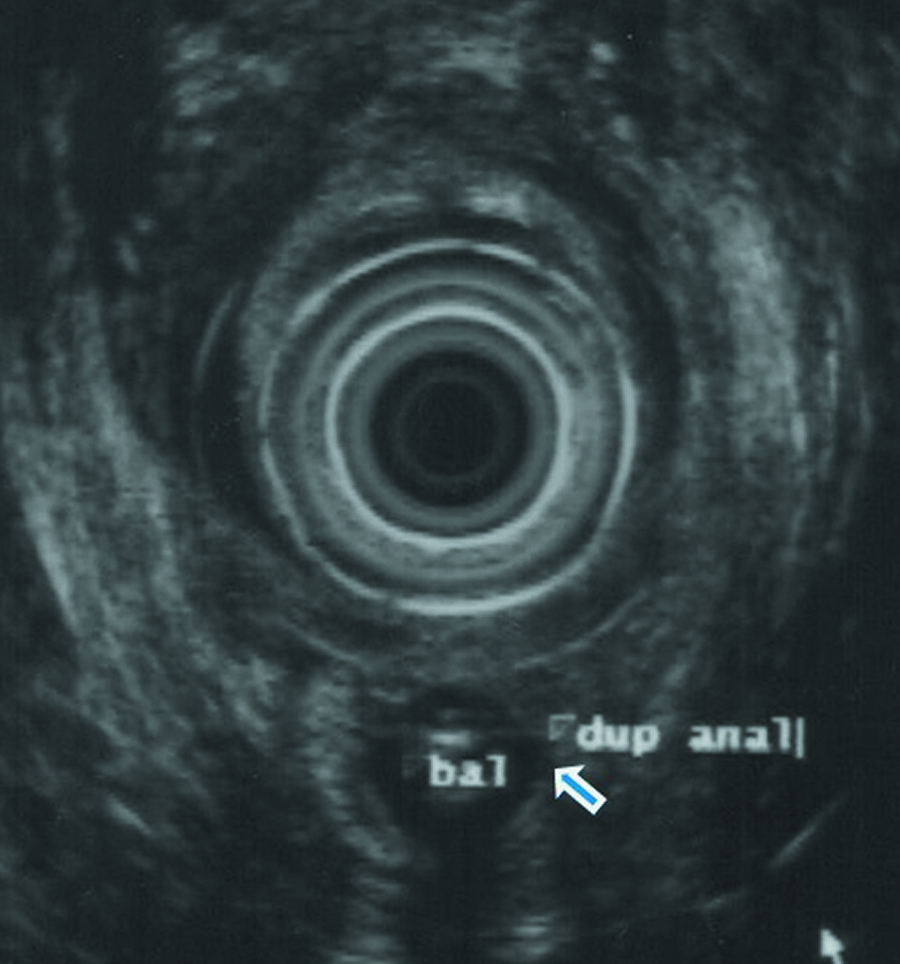

Fisiológicamente, la materia fecal pasa a través del canal anal, que se conecta directamente con el recto, donde se almacenen los residuos antes de dejar el cuerpo. En teoría, la mujer podría haber sido capaz de excretar a través de ambos canales. No obstante, los médicos determinaron que su segundo canal, de tan solo 3 centímetros de profundidad y un centímetro de ancho, no estaba vinculado con la pared rectal, aunque se hallaba separado del canal principal sólo por la piel.